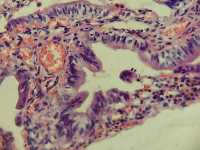

胆囊长8直径3.2囊壁粗糙

图1

慢性胆囊炎

同意,黏膜上皮增生,少数有轻度非典型性。